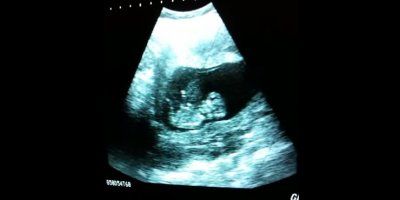

Zadivljujuća ultrazvuk snimka – beba koja se igra!